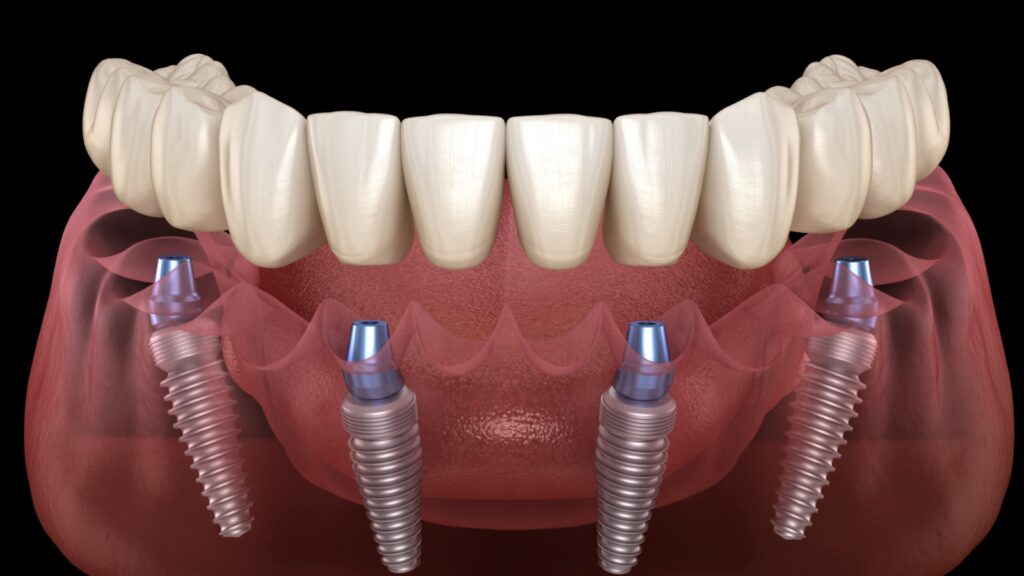

Elevate your dental care journey with our membership program, specifically designed for patients seeking teeth implants. As a member, you’ll benefit from reduced pricing on implant procedures, priority scheduling for consultations and treatments, and continuous follow-up care to ensure the best outcomes. Join today to access top-tier dental implant services and enhance your smile with confidence.